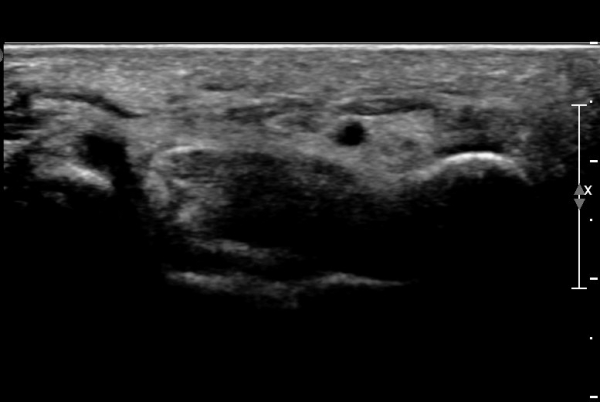

Á¶±Ý ´õ ¸»´ÜÀ¸·Î À̵¿ÇÏ´Ï Äá¾Ë»À ÇÇÁú°ñ ¿¬¼Ó¼º ¼Ò½ÇÀÌ °üÂûµÊ(»çÁö 3),

Äá¾Ë»À Á¾´Ü¸é°Ë»ç¿¡¼­ Äá¾Ë »À ±ÙÀ§ºÎÀÇ ÇÇÁú°ñ °ß¿­ÀÌ °üÂûµÊ(»çÁö 4).